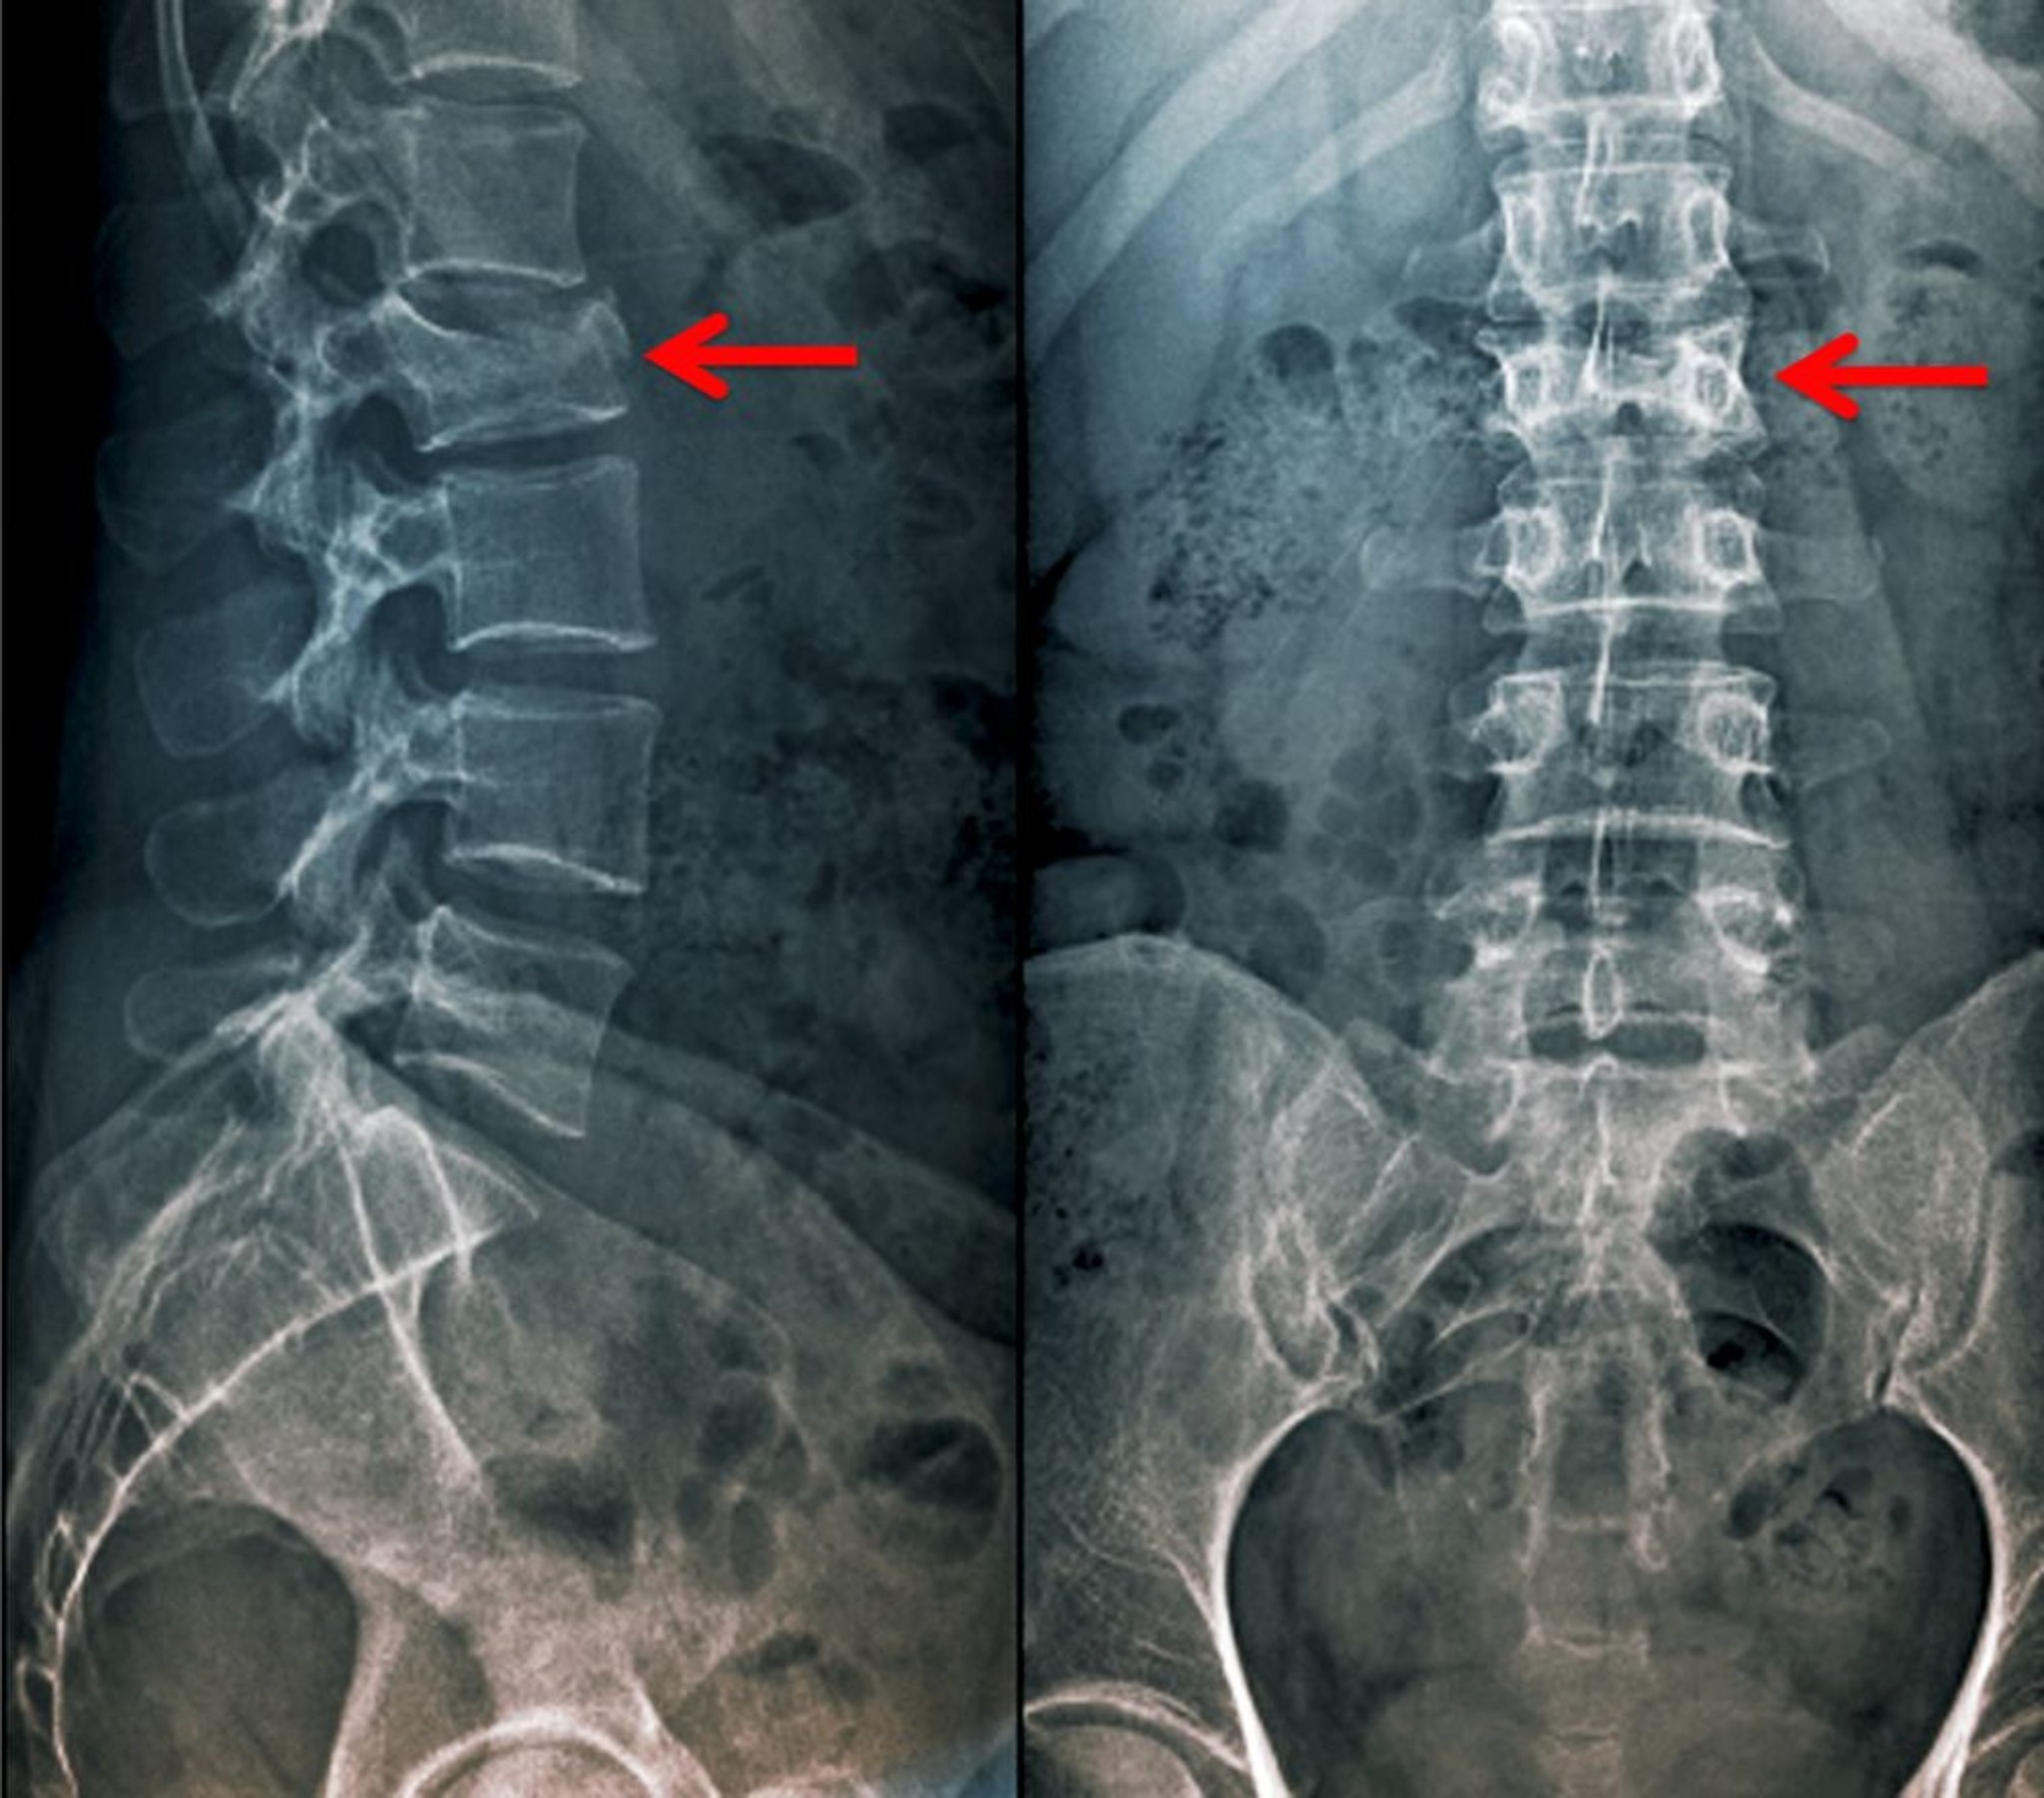

Incidences antéropostérieure et de profil d'une fracture par compression

Cette fracture par compression de la 2e vertèbre lombaire est visible comme une perte de la hauteur du corps vertébral en incidence antéropostérieure ainsi qu'en incidence de profil.